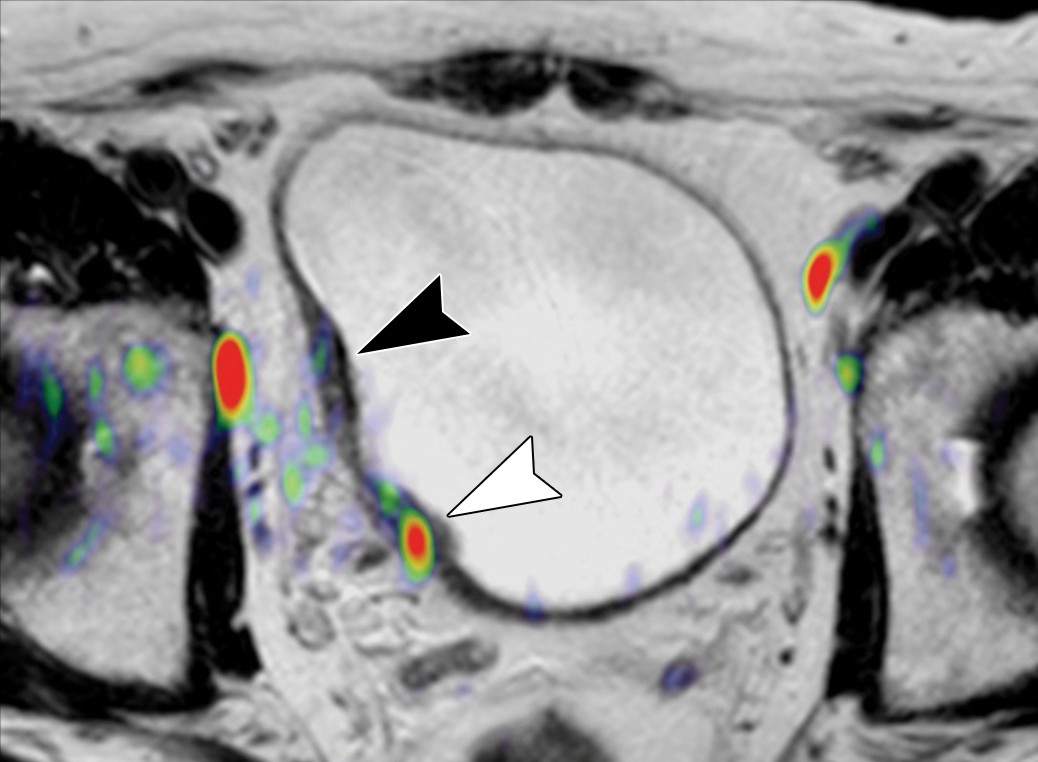

• Gerekirse PET/BT:

Özellikle şüpheli lenf nodları varsa ya da uzak organlara metastaz şüphesi varsa yapılır.

PET/BT Ne Zaman Yapılır?

• BT veya MR’da şüpheli lenf nodu görülürse

• Uzak organ metastazı şüphesi varsa

• Kemoterapi öncesi hastalığın yayılımını netleştirmek gerekiyorsa

• Standart BT’nin yeterli bilgi vermediği durumlarda

Avrupa Üroloji Derneği (EAU) kılavuzları, PET/BT’nin sadece şüpheli olgularda yapılmasını önerir.